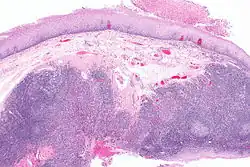

![]() | |

| Oral cancer on the side of the tongue, a common site along with the floor of the mouth | |